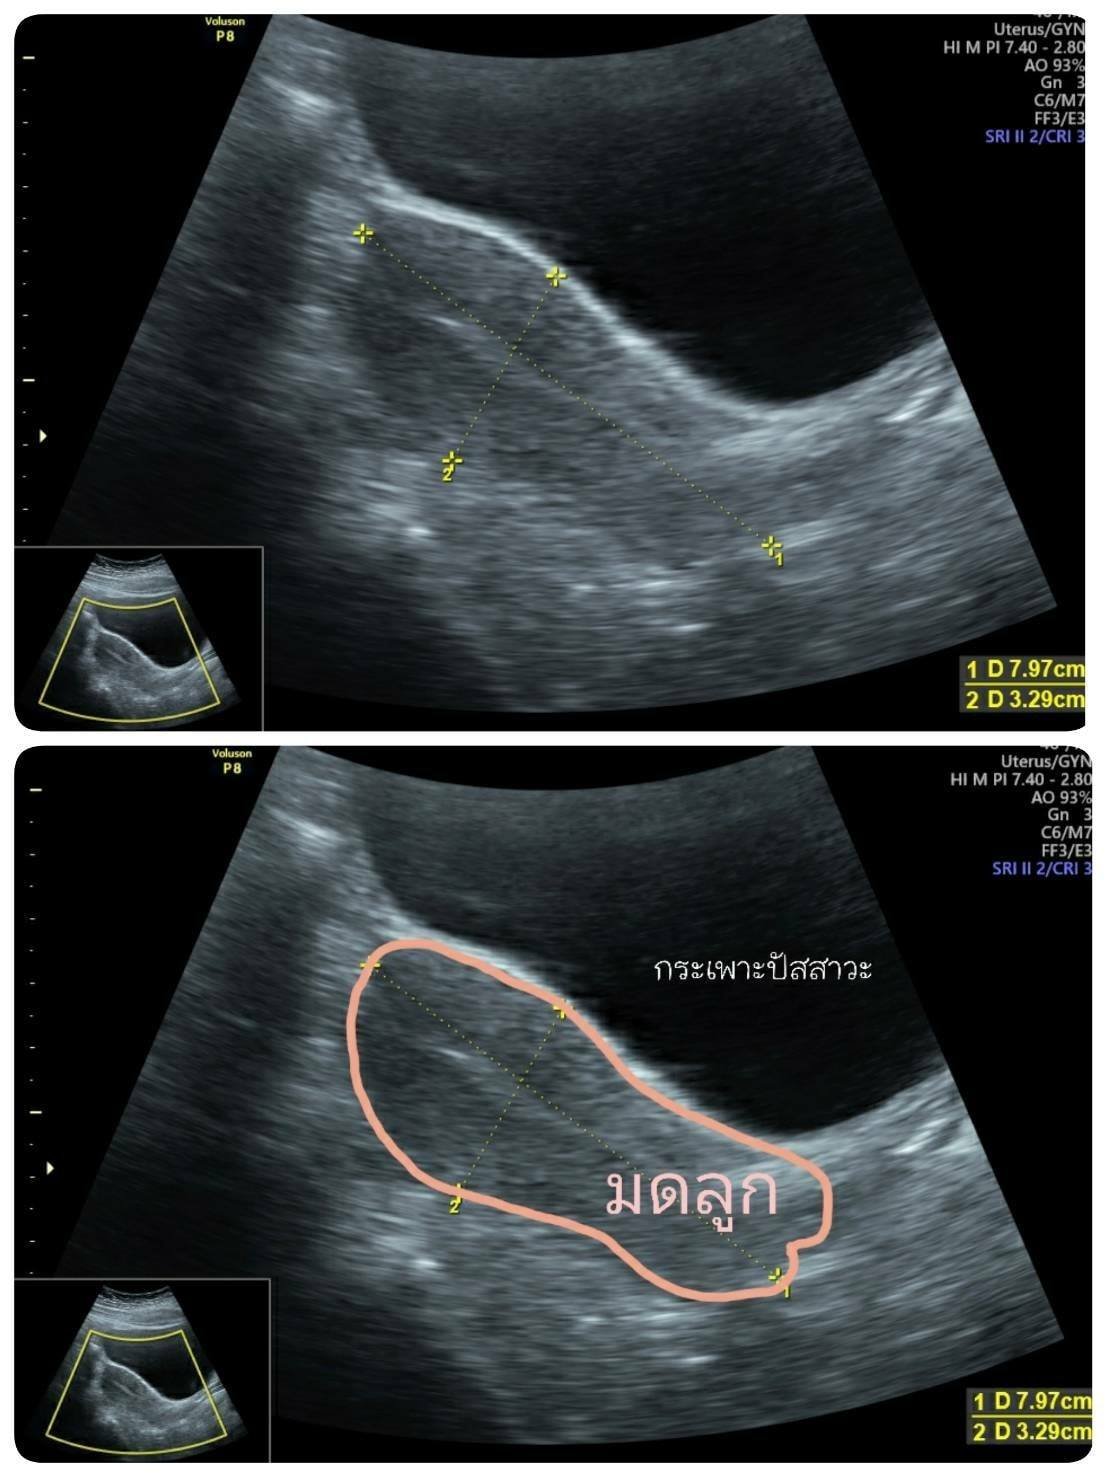

ภาพตรวจอัลตร้าซาวด์มดลูก ผ่านทางหน้าท้อง

ตรวจหาเนื้องอก ถุงซีสต์ วัดขนาดมดลูก